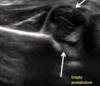

What tests are done to screen for DDH in the NIPE?

When examining, look for ***symmetry*** in the hips, leg length, skin folds and hip movements * ***Ortolani test*** * ***Barlow test*** Need US if clicking or clunking. Clunking more likely to be DDH

After screening how is DDH diagnosed?

**US Hips:** if child has risk factors or positive screening **Xrays:** if \>4.5 months old this is first line not US